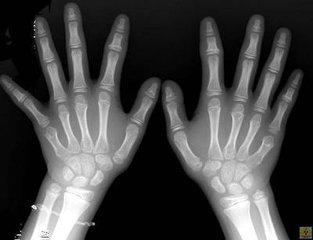

(图:罗先生双手、双足关节痛风石明显)

查体:双手指关节鹌鹑蛋大小痛风石、左膝关节胡豆大小痛风石、双手指鸡蛋大小痛风石、双足跖趾关节胡豆大小痛风石、左足后跟胡豆大小痛风石,关节活动受限,肾功能不全。

(图:罗先生治疗后的手部X光)

章晓辉主任通过中医微创可视针刀镜技术,将罗先生各关节处痛风石逐步清除,由于数量较多,且罗先生病情比较严重,无法快速清除。因此,在清除部分结石后,章晓辉主任安排罗先生进行科学疗法治疗,经过第一次治疗,罗先生感觉浑身轻松许多,关节疼痛在慢慢减轻。治疗一个疗程后,罗先生的病情初步得到缓解,双手指关节僵硬感缓解,肿痛现象有所消退,多关节细小痛风石基本溶解。治疗二个疗程后,罗先生的多关节肿僵现象逐渐好转,痛风石也清除了许多,肾功能恢复正常,关节活动度提高。为了巩固加强疗效,章晓辉主任还为罗先生进行了食疗调理辅助治疗,达到内外平衡、巩固临床治疗效果的目的。三个疗程的治疗结束后,罗先生来院复查,数据显示各项指标均达正常范围,章晓辉主任表示已达临床 标准。离院前,章晓辉还嘱咐罗先生,回去要注意保暖,饮食要均衡,多多休息,做些有氧运动,帮助身体恢复到最佳状态。